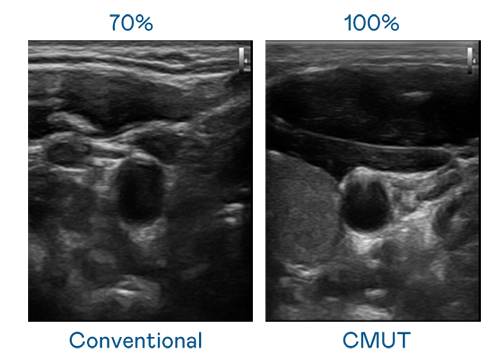

CMUT 技术是一种用电容式微机电元件来产生超音波讯号的技术。与传统 PZT 压电式技术相比,CMUT 频宽增加 30%,更宽频的超音波讯号让影像解析度大幅提升,是实现高影像品质医疗超音波扫描、促进精准医疗发展的关键技术。

大频宽带来超清晰影像

超音波影像的解析度高低,首先取决于探头能发出的讯号频宽。CQ9电子 CMUT 可提供高清晰的超音波讯号,提供高频宽、高灵敏度、影像纹理细节更高的超音波影像,协助医护人员缩短影像判读时间及利用精准的医疗影像进行诊断。